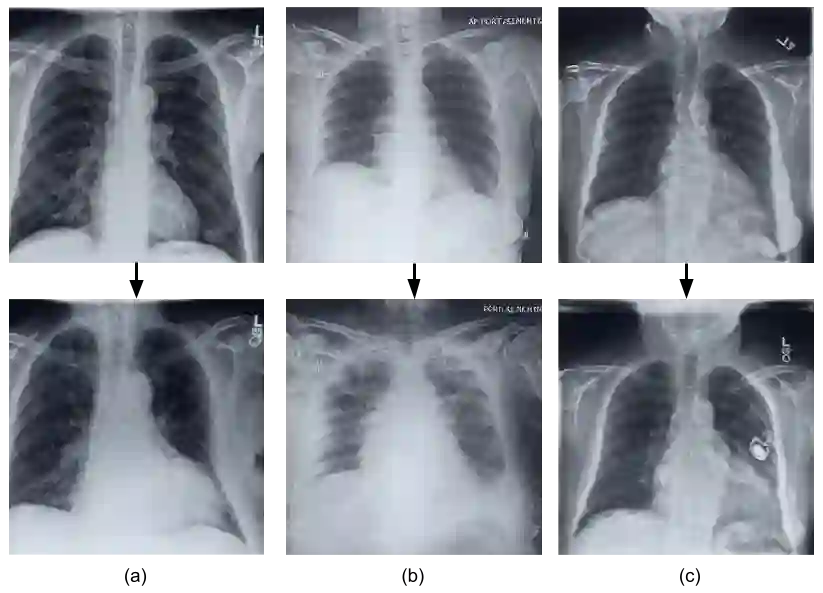

Deep learning models used in medical image analysis are prone to raising reliability concerns due to their black-box nature. To shed light on these black-box models, previous works predominantly focus on identifying the contribution of input features to the diagnosis, i.e., feature attribution. In this work, we explore counterfactual explanations to identify what patterns the models rely on for diagnosis. Specifically, we investigate the effect of changing features within chest X-rays on the classifier's output to understand its decision mechanism. We leverage a StyleGAN-based approach (StyleEx) to create counterfactual explanations for chest X-rays by manipulating specific latent directions in their latent space. In addition, we propose EigenFind to significantly reduce the computation time of generated explanations. We clinically evaluate the relevancy of our counterfactual explanations with the help of radiologists. Our code is publicly available.

翻译:用于医学图像分析的深层学习模型由于其黑盒性质而容易引起可靠性问题。 为了阐明这些黑盒模型, 先前的工作主要侧重于确定输入特征对诊断的贡献, 即特性归属。 在这项工作中, 我们探索反事实解释, 以确定模型的诊断依赖模式。 具体地说, 我们调查胸部X光中的变化特征对分类器输出的影响, 以了解其决定机制。 我们利用基于StyleGAN(StyleGANEX)的方法, 通过在它们潜藏空间操纵特定的潜伏方向来为胸部X光创造反事实解释。 此外, 我们建议 EigenFind 大幅缩短生成解释的计算时间 。 我们临床评估了我们在放射学家的帮助下反事实解释的关联性。 我们的代码是公开的 。